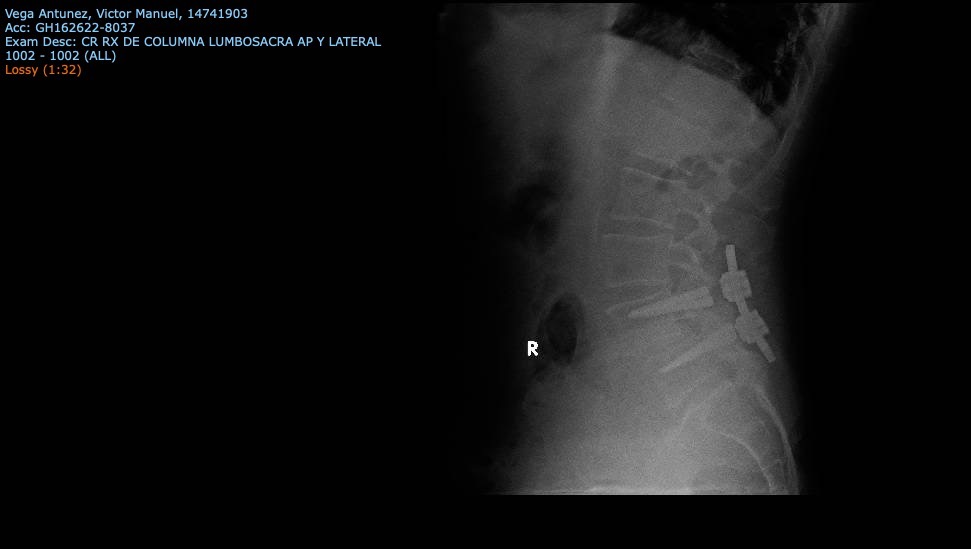

Es extremadamente raro que los tornillos se rompan todos. Se puede romper uno, o dos, pero cuatro es un caso especial y preocupante.

Él fue operado por la Seguridad Social en Agosto de 2019, pero sufrió una caída catastrófica en Mayo de 2021, donde el implante que le fue puesto, sufrió la rotura de todos los tornillos de titanio que le habían colocado (cuatro), con lo que la placa que los unía, quedó flotando. Esto le ha provocado mucho dolor y complicaciones, llegando incluso a no poder caminar, y esto se ha agravado en los últimos días.

Lo llevamos a revisar con el cirujano que lo operó, que es un Doctor muy reconocido y un especialista en su ramo, el cual nos indicó que necesita una nueva intervención, con un doble propósito, el retirar los cuerpos de los tornillos de las vértebras (que es una tecnología alemana y la cual no la tiene la Seguridad Social, así como el instrumental médico y el Fluoroscopio, que tampoco lo tiene la Seguridad Social.

Con el instrumental médico que nos recomienda el Doctor, se podrían retirar los cuerpos de los tornillos sin afectar a las vértebras, que se encuentran con hueso degradado ya, y eso podría provocar una parálisis de sus piernas.